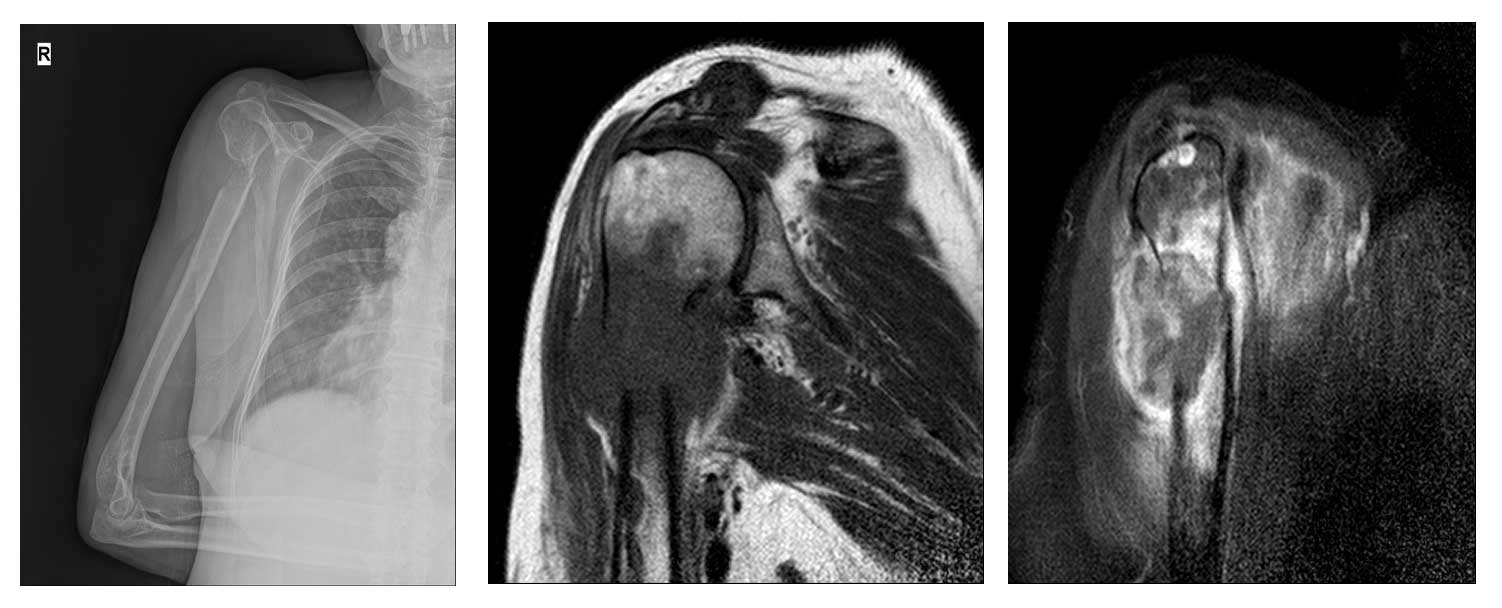

Ameliyat Öncesi: Röntgende sağ humerus üst uçta harabiyet ve kırık, MR’da kemiğin dışına taşmış metastaz odağına eşlik eden yaygın ödem görülmekte.